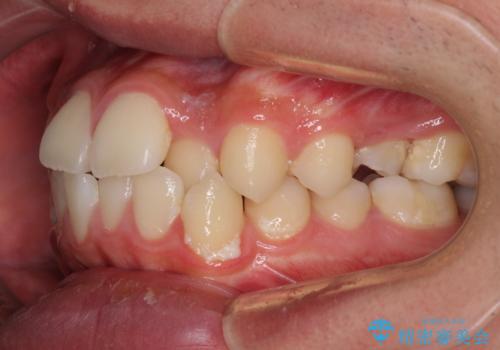

- 前歯のデコボコと口元の突出感を気にして来院された患者様です。

上下前歯がくちばしのように突出していたため、上下左右の第一小臼歯4本を抜歯し、ワイヤー装置にて矯正治療を行うこととしました。

左上は第二小臼歯が90度捻れており、状態が良くない歯であったため、左のみ第二小臼歯を抜歯することとしました。